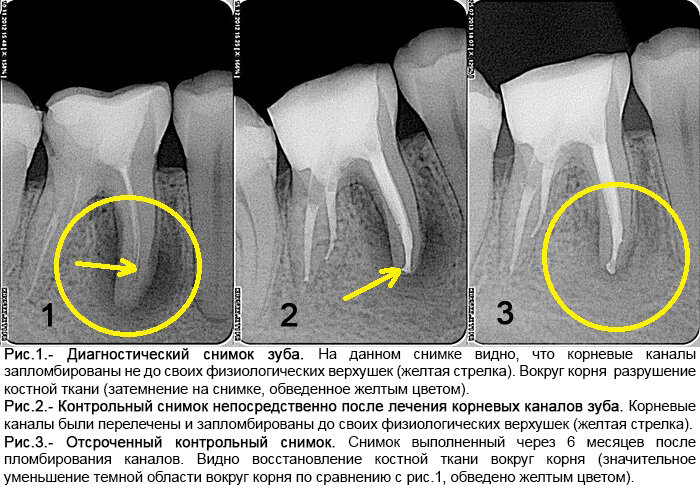

Причиной периодонтита могут быть инфекция, травма, действие токсичных веществ. Чаще периодонтит является исходом кариеса или пульпита, при котором пульпа (нерв) уже не может служить барьером для токсичных продуктов и они проникают за верхушку зуба. Периодонтит как и пульпит в большинстве случаев развивается на начальных стадиях практически незаметно, зачастую после острого воспаления пульпы и при отсутствии соответствующего лечения.

При длительном течении процесса околоверхушечная костная ткань постепенно разрушается, образующийся дефект замещается грануляционной тканью.

В одних случаях у больного вокруг грануляционной ткани образуется плотная фиброзная капсула — зубная гранулема, которая со временем может превратиться в кисту, заполненную гноем и продуктами воспаления.

- Делать контрольные снимки и окончательный результат.

По истечении нескольких месяцев врач делает рентгеновский снимок. Если периодонтит вылечен, убирает временную пломбу, заполняя корневой канал постоянным материалом, восстанавливая первоначальный внешний вид коронковой части.